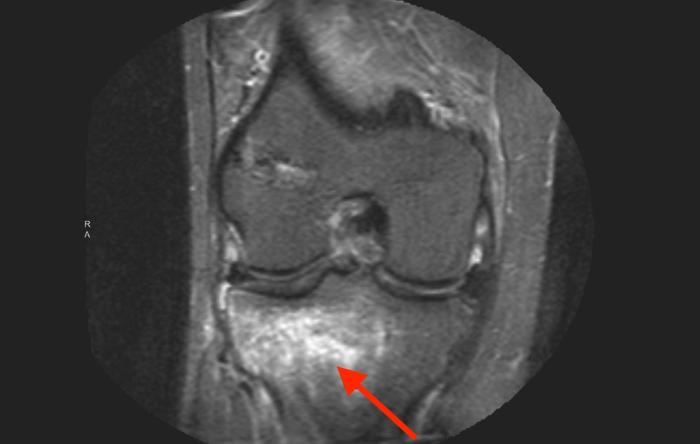

ACL Reconstruction Surgery Explained & Picking The Right ACL Graft

When it comes to selecting the best possible ACL...

ACL Repair vs. Reconstruction: Here’s the Latest

Anterior cruciate ligament (ACL) primary repairs...